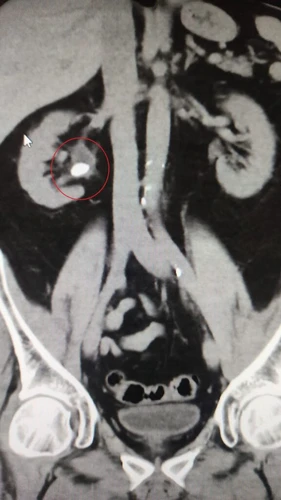

Resim 2. Koronal kesitli BT'de sağ börekteki taş görülmekte.

Çekilen bel MR’ında sağ böbrek pelvisinde üreter girişinde 1.5 cm çapında böbrek taşı tespit edildi.